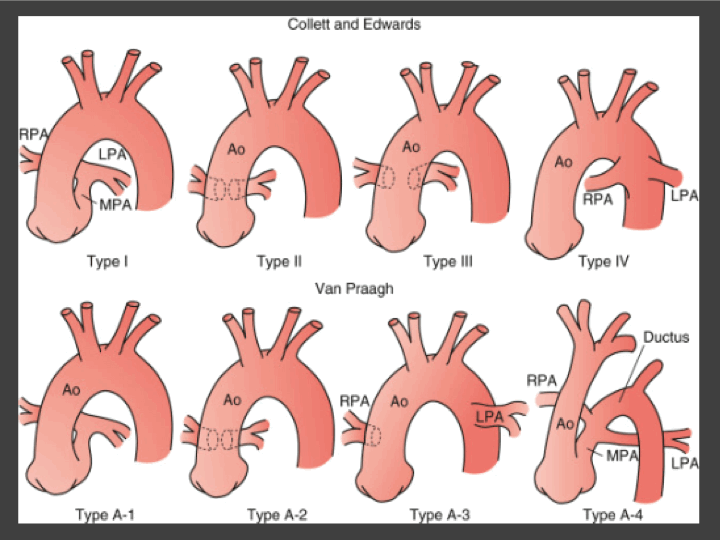

Tronc arteriel commun (TAC)

Truncus Arteriosis

- Aortie et Tronc pulmonaire à départ commun

- VSD

- Type I le plus fréquent (Tronc Pulm partant de la face postérieure gauche TAC)

- 1/3 associé à des arcs aortiques droits, avec cardiomégalie et vasculature pulmonaire augmentée (contrairement au fallot)